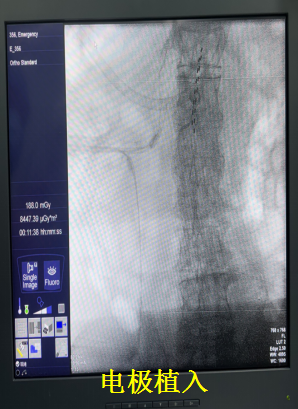

西院二病区尚亮主任团队在了解到患者的情况后,卫娜副主任立即组织多学科专家会诊。鉴于患者的特殊情况,神经外科缪星宇主任与张翼博士等团队成员,经过精准评估和充分讨论,决定采用脊髓电刺激镇痛疗法。该疗法通过在脊髓硬膜外腔植入电极,将外界电刺激传递到脊髓,干扰疼痛信号传导,从而达到缓解疼痛的目的。其具有创伤小、可逆、可调节等优点,特别适合高龄、身体状况较差的患者。

局部麻醉后,手术顺利进行,电极成功植入到预定位置。当开启脊髓电刺激设备的那一刻,老人惊喜地发现,折磨他多年的疼痛竟然减轻了一大半。他激动地表示:“好久没有这么轻松了。” 术后,尚亮主任团队和缪星宇主任团队每日查看患者恢复情况,根据患者感受及时调整刺激参数,确保治疗达到最佳效果。